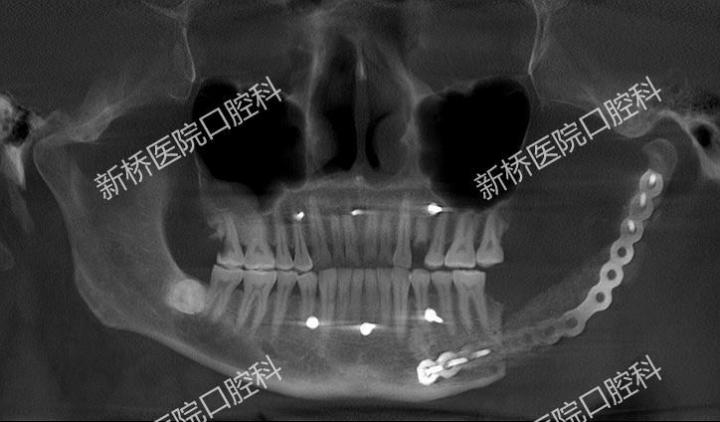

诱导膜技术修复颌骨缺损

骨水泥主要由聚甲基丙烯酸甲酯(PMMA)粉末和液态甲基丙烯酸甲酯(MMA)单体组成。骨水泥具有良好的生物相容性、化学稳定性和较高的机械强度,且在固化过程中放热较少,对周围组织影响较小。

多是在骨科当中应用,用于处理骨折、关节病变或骨质疏松等问题。它的主要原理就是在植入之后,能形成一层诱导膜,这层膜内部可以产生成骨微环境,诱导成骨,膜内填入骨松质后就可以在它的诱导下形成新骨。因此骨水泥主要有填充缺损、支撑以及诱导成骨的作用。